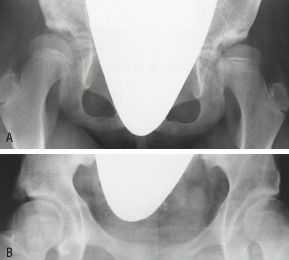

Principal alteração radiográfica

Achado radiográfico com obliquidade aumentada e perda da concavidade acetabular.

Diagnóstico em crianças maiores de 1 ano

Através de exames de imagem, como radiografia, e testes clínicos específicos.

Sinais radiográficos tardios

Desenvolvimento de osteoartrite e subluxação do quadril.